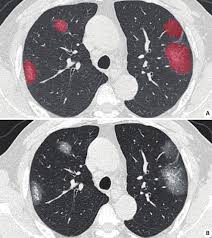

彩神v肺衛(wèi)士 - 肺部疾病智能檢測平臺

查看詳情>>

針對肺結節(jié)、肺炎等肺部疾病的CT影像智能分析,協(xié)助醫(yī)生快速診斷。